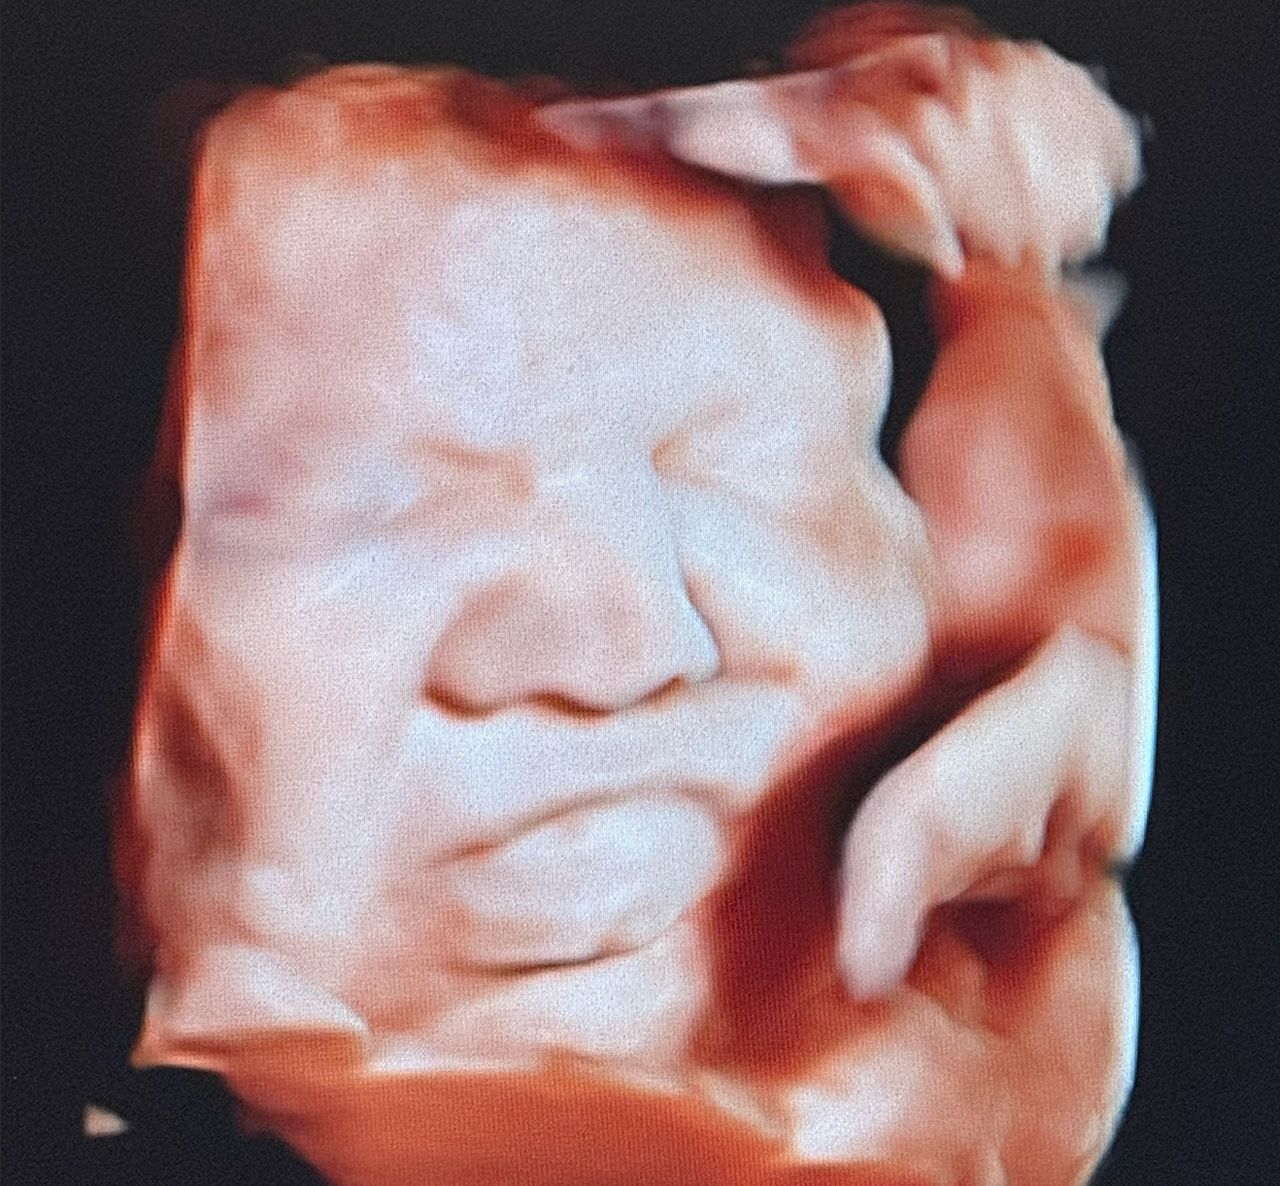

Mi occupo della gestione delle gravidanze fisiologiche e a rischio ed eseguo ecografie ostetriche in tutti i trimestri di gravidanza, tra cui ecografia di datazione, bitest e traslucenza nucale, ecografia morfologica, ecografia del III trimestre con flussimetria fetale, cervicometria ed ecografie 3D/4D, fondamentali per una corretta diagnosi e per il monitoraggio della salute materno-fetale.

ecografia ostetrica 3D/4D 215 €